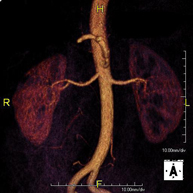

Prova diagnòstica no invasiva que consisteix en l'estudi de l'artèria aorta abdominal i de les artèries ilíaques, amb l'obtenció d'imatges d'alta definició anatòmica mitjançant l'ús d'un camp electromagnètic i ones de ràdio (amb un emissor i un receptor). És indispensable l'ús de contrast paramagnètic (Gadolini). No utilitza radiació ionitzant. La qualitat de les imatges permet realitzar reconstruccions en 2D i 3D. Aquesta prova està especialment indicada com a estudi prequirúrgic (mapa vascular) abans d'intervencions percutànies o quirúrgiques d'aorta abdominal i artèries ilíaques, per a l'estudi complementari en pacients amb isquèmia de membres inferiors, etc. - Angio RM Arterial d'extremitats inferiors

Prova diagnòstica no invasiva que consisteix en l'estudi vascular del sector aorto-ilíac i dels vasos arterials de les dues extremitats inferiors, am l'obtenció d'imatges d'alta definició anatòmica mitjançant l'ús d'un camp electromagnètic i ones de ràdio (amb un emissor i un receptor). És indispensable l'ús de contrast paramagnètic (Gadolini). No obstant, no utilitza radiació ionitzant. La qualitat de les imatges permet realitzar reconstruccions en 2D i 3D. Està especialment indicat en aquells pacients en els que hi ha sospita de malaltia vascular a les dues extremitats, en pacients amb malaltia vascular de les dues extremitats com a mapa vascular abans del tractament (percutani o quirúrgic), com a mapa vascular prequirúrgic en pacients amb lesions òssies o musculars que requereixin cirurgia, etc. - Angio-RM d'Artèries renals

Prova diagnòstica no invasiva que consisteix en l'estudi de l'artèria aorta abdominal per obtenir imatges d'alta definició anatòmica mitjançant l'ús d'un camp electromagnètic i ones de ràdio (amb un emissor i un receptor). És indispensable l'ús de contrast intravenós paramagnètic (Gadolini). No obstant, no utilitza radiació ionitzant. La qualitat de les imatges permet realitzar reconstruccions en 2D i 3D. Està indicat en aquells pacients amb malaltia vascular (Aterosclerosi), per a l'estudi d'aneurismes, en estudis prequirúrgics de lesions adjacents a l'aorta abdominal com "mapa" vascular, etc. - Angio-RM Aorta ilíaca

Prova diagnòstica no invasiva que consisteix en l'estudi de l'artèria aorta abdominal per obtenir imatges d'alta definició anatòmica mitjançant l'ús d'un camp electromagnètic i ones de ràdio (amb un emissor i un receptor). És indispensable l'ús de contrast intravenós paramagnètic (Gadolini). No obstant, no utilitza radiació ionitzant. La qualitat de les imatges permet realitzar reconstruccions en 2D i 3D. Aquesta prova està especialment indicada com estudi prequirúrgic (mapa vascular) abans d'intervencions percutànies o quirúrgiques d'aorta abdominal, per a l'estudi complementari en pacients amb isquèmia de membres inferiors, etc. - Angio-RM d'Artèries renals

Prova diagnòstica no invasiva que consisteix en l'estudi de l'artèria aorta abdominal per obtenir imatges d'alta definició anatòmica mitjançant l'ús d'un camp electromagnètic i ones de ràdio (amb un emissor i un receptor). És indispensable l'ús de contrast intravenós paramagnètic (Gadolini). No obstant, no utilitza radiació ionitzant. La qualitat de les imatges permet realitzar reconstruccions en 2D i 3D. Aquesta prova està indicada, per exemple, en pacients que pateixen d'HTA refractària al tractament, en pacients amb lesions renals per obtenir un mapa vascular prequirúrgic, etc. - Angio-RM Arterial d'extremitats inferiors

Prova diagnòstica no invasiva que consisteix en l'estudi de l'artèria aorta abdominal per obtenir imatges d'alta definició anatòmica mitjançant l'ús d'un camp electromagnètic i ones de ràdio (amb un emissor i un receptor). És indispensable l'ús de contrast intravenós paramagnètic (Gadolini). No obstant, no utilitza radiació ionitzant. La qualitat de les imatges permet realitzar reconstruccions en 2D i 3D. Està especialment indicada en pacients amb sospita de malaltia vascular de les dues extremitats, en pacients amb malaltia vascular de les dues extremitats com a mapa vascular abans del tractament (percutani o quirúrgic), com a mapa vascular prequirúrgic en pacients amb lesions òssies o musculars que requereixin cirurgia, etc. - Angio-RM Lesión partes blandas